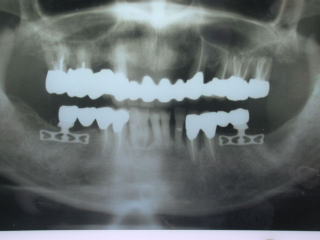

●インプラントのレントゲン写真例

上の前歯の例です。

左上の入歯が見た目、噛合せとも満足できず、左上前歯部にインプラントを植立。

入歯をブリッジにすることにより不満を解消できました。